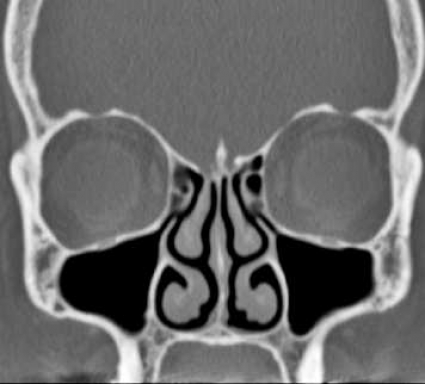

Initiala fantomstudier och pilotundersökningar visade, som förväntat, att bildkvaliteten med lågdosprotokollet blev sämre än med standardprotokollet, men den bedömdes ändå som fullt tillräcklig för den diagnostiska uppgift som avses med en konventionell röntgenundersökning av bihålorna (Figur1). Det diagnostiska värdet av lågdos-DT bedömdes av både radiologer och örondoktorer som klart överlägset värdet av en vanlig röntgenundersökning, och dosberäkningar visade också att stråldosen var lägre för lågdos-DT än för konventionell röntgenundersökning.

Resultaten visar klart att lågdos-DT ger bra visualisering av samtliga näsans bihålor, och man kunde med lätthet både påvisa och utesluta engagemang av såväl frontalsinus som sfenoidalsinus och inte minst av etmoidalsinus, ett område där den konventionella teknikens tillkortakommanden är väl kända. Lågdos-DT visade sig också möjliggöra en diagnostisk bedömning av anatomiska nyckelstrukturer såsom infundibulum och frontonasala recessen.

Användandet av lågdos-DT innebär sålunda inte bara en säkrare diagnostik av bihåleförändringar än med vanlig röntgenundersökning, utan man får också viktig tilläggsinformation, som inte kan erhållas med vanlig röntgenundersökning. Även möjligheten att visualisera små, men kliniskt relevanta anatomiska avvikelser (tex concha bullosa, Haller-celler och dysplasier), postoperativa förändringar, benförändringar vid kronisk sinuit och odontogena orsaker till sinuit, gör lågdos-DT klart överlägsen konventionell röntgenundersökning vid sinuit (Figur2).